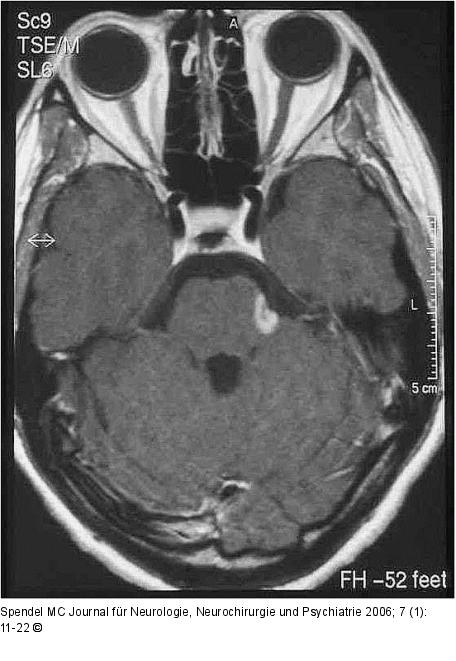

Abbildung 1: Enzephalitischer Plaque - Nervus trigeminus MRT mit enzephalitischer Plaque in der Eintrittszone des Nervus trigeminus links. |

MRT mit enzephalitischer Plaque in der Eintrittszone des Nervus trigeminus links. |